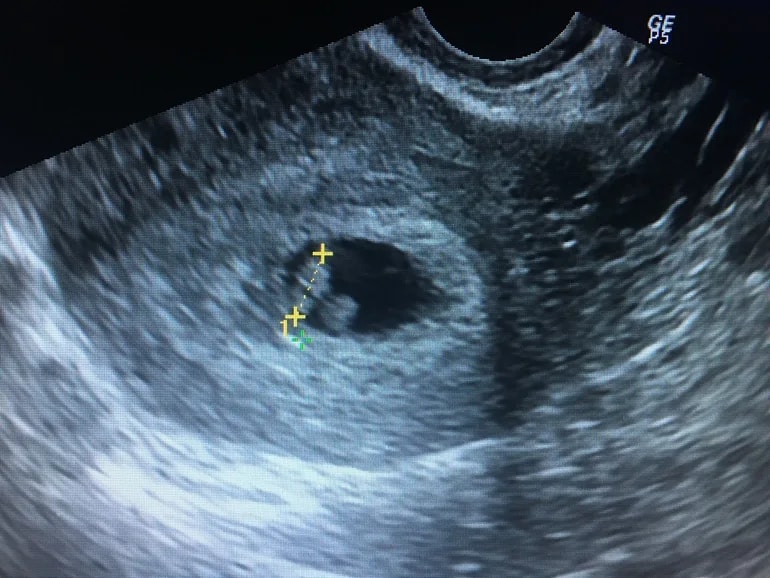

и вот на 28 дпп не выдерживаю, иду на узи в другое место раньше заявленного срока (меня ждут на 33дпп)

хгч 35900

Пя, жм, с+

все соответствует срокам! Сердечко стучит, всё на месте.

Встаем на учет, ждем первый скрининг.